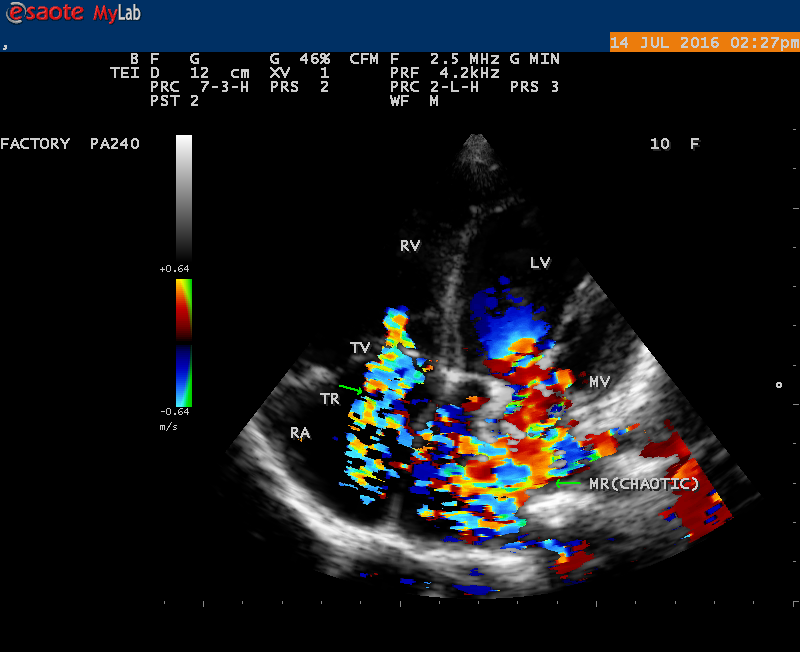

A 10 year female child was referred for echocardiographic evaluation with an apical systolic murmur. The child was having recurrent episodes of rheumatic fever (febrile illness with joint pains) at the age of 5-6 years and taken some treatment from the local medical practitioner, but she was not taken penicillin prophylaxis earlier. The child was remained afebrile for long period and no precipitating factors of infective endocarditis such as dental or genitourinary procedures in the past. General examination revealed normal growth and development, no cyanosis and clubbing and peripheral signs of infective endocarditis such s Osler’s nodes, Janeway lesions, Roths spots and splinter haemorrhages are not present and they are relatively rare in children. Physical examination revealed a grade 3/6 , blowing, high pitched, holosystolic murmur with a constant intensity and duration on dynamic auscultation and loudest at the apex with a radiation to left axilla and transmitted to the left infrascapular area and vertebral coloumn and it is due to the flow generating the murmur is directed posterolaterally within the left atrial cavity, suggesting the murmur of mitral regurgitation due to the rupture of chordae tendineae of anterior mitral leaflet. Blood culture revealed normal. Blood chemistry revealed the positive serum ASO titer, suggesting a recent streptococcal infection and other parameters are normal. X- ray chest reveled moderate cardiomegaly and ECG revealed a left ventricular volume overload pattern of eccentric hypertrophy due to LV dilatation as a result of severe mitral regurgitation and a normal rhythm. Transthoracic echocardiography revealed a giant vegetation ‘popcorn’ like in Figures 1,3 and 4 and ‘cucumber’ like in Figure 2, mainly attached to base and apical portion of anterior mitral leaflet as shown in Figure 31 and manifested in various size and shapes as shown in Figures 1 to 33. A flail anterior leaflet with a disorganized mitral regurgitation jet as shown in Figure 16 and 21 and the posterior leaflet is embedded with vegetation and resulting in ‘kissing forms’ as shown in Figures 13, 14 and 15 in echocardiography imaging. Tricuspid valve is also thickened and calcified as shown in Figure 2 in addition to thickened and calcified mitral leaflets, suggesting an underlying rheumatic etiology predisposing to the formation of vegetation. The child was given 1.2 million units of intramuscular benzathine penicillin injection as a therapeutic and initial prophylaxis dose for rheumatic fever and advised every 3 weeks for life long. Small doses of digoxin and diuretics are also prescribed and advised early surgery (mitral valve replacement) Transthoracic 2D images are as in Figures 1 to 33 are given below

The most common and direct evidence of infective endocarditis is the vegetation and it begins as a microscopic focus of infection and gradually grows into a conspicuous mass. It is typically an irregularly shaped, highly mobile, echogenic mass attached to the free edge of a valve leaflet ( most commonly at the coaptation line) and tends to develop on the ‘upstream’ side of the valve leaflets ( ie, the ventricular side of aortic valve and the atrial side of mitral and tricuspid valves. They may be seesile or pedunculated, but usually has an oscillating or fluttering motion, a typical feature of most vegetations. Vegetation move with the leaflet in a more chaotic (‘oscillating’) manner and it may prolapse through the valve into the LV (left ventricle) as it opens as shown in Figures 3, 4 and 16 and into LA (left atrium) as it closing (Figure 5 and 6) . The mass of vegetation is typically homogeneous with echogenicity similar to that of the myocardium. The infectious process often alter the valvular structure and function. Extensive involvement of the leaflet may result in chordal rupture, leading to severe regurgitation as shown in Figure 21 . Direct and typical signs of RMCT (ruptured mitral chordate tendineae) were chain-flail or whiplash-like changes and had an incidence of 86.7%, causing severe regurgitation and mitral chordal rupture is the leading cause of flail mitral leaflet[30]. A large vegetation may obstruct the valve orifice as shown in Figure 1 and 2 , sometimes termed as “obstructive-type bacterial endocarditis” and producing a functional valve stenosis ( Ping-Pong mitral stenosis [31]) similar to left atrial myxoma as shown in Figure 29.

The shape of vegetation varies in this child as ‘popcorn’ like (Figures 1,3 and 4 ), rod-shaped (Figure ), basket shaped (Figure 7 )[33-Figure 13.3], ‘baby in hand’ appearance (Figure 18), ‘cucumber shaped (Figure 2 ) and a ‘bunch of plantain’appearance (Figure 33 ), ring shaped (Figure 19 }, bileaflet structure (Figure 9 )with bileaflet MR jet as shown in Figure 10 . and kissing forms (Figure 13 - parasternal long axis view, Figure 14 - apical four chamber view and Figure 15 - short axis view)

‘Flail’ Mitral Regurgitation (MR)

The anatomic disruption of a portion of the mitral valve apparatus dueto the underlying rheumatic valvulitis with predisposing infective endocarditis which form a vegetation , resulting an eccentric regurgitation jet with orientation opposite in direction of the leaflet having the anatomic defect such as ‘flail’. In the presence of ‘flail leaflet’, the mitral regurgitant spectral signal may have an atypical appearance and the flail portion oscillate in the spectral signal of regurgitant flow stream to produce a ‘tiger stripe’ appearance as shown in Figure 27. associated with ‘whistling’ sound on auscultation[33-Figure 11.85]. The mitral regurgitation (flail MR) jet is chaotic as shown in Figure 26, highly eccentric (Figure 22) and disorganized with one component behind the anterior mitral leaflet and the second component directed towards posterior immediately as in Figure 21 [33- Figure 11.79].

The severity of eccentric MR is underestimated because of coanda effect. If the regurgitant jet area fills < 20> 40% indicate severe regurgitation. The vena contracta ( the neck or narrowest portion of the jet), typically imaged perpendicular to the commissural line in parasternal long axis and apical four chamber views is well defined in both central and eccentric jets, but not in chaotic, disorganized jets due to flail leaflets. Its width < 3> 7 mm defines severe MR and a mean value of > 8mm indicates severe functional MR. The flow convergence method based on PISA (proximal isovelocity surface area) may not applicant for eccentric and multiple jets or complex and elliptical regurgitant orifices to assess the severity of mitral regurgitation.. The adaptation of LV to the increased volume overload is reflected by LV dimensions and ejection fraction.. In chronic compensated phase, the forward stoke volume is maintained through an increase in LV ejection fraction >65% and the patient could be asymptomatic. In chronic decompensated phase of MR, the forward stroke volume decreases and the LA pressure increase significantly. The patient may be still asymptomatic and the LV ejection fraction may be in the low normal range despite the presence of significant muscle dysfunction. The contractile function decreases silently and become irreversible. In the current guidelines, surgery is recommended in asymptomatic patients with severe organic MR when the LV ejection fraction is ≤ 60%. However, in acute stage, the LV ejection fraction increases in response to the increased preload. The end-systolic diameter is less preload dependent than the ejection fraction and it may be more appropriate to monitor the global LV function. The end-systolic diameter > 45 mm also indicate the need for mitral valve surgery [43]. In this child, the LVESD (end-systolic diameter) is 30.7 mm and the ejection fraction (EF) is 66% as shown in Figure 19. New parameters are currently available for a better assessment of LV function. A systolic tissue Doppler velocity measured at the lateral annulus <10>40-50mm) may predict the onset of atrial fibrillation and poor prognosis in patients with organic MR[48]. The excess regurgitant blood entering in the LA may induce acutely or chronically a progressive rise in pulmonary pressure and the presence of TR (tricuspid regurgitation) as shown in Figures 26 and 28 permits the estimate of systolic pulmonary arterial pressure and mitral valve surgery is recommended when it is > 50 mmHg at rest and LA reverse remodeling may occur after surgery. The severe TR may cause a decrease in hepatic vein systolic velocity and systolic flow reversal may occur as shown in Figure 32 and its sensitivity is 80% [49]. The TR (tricuspid regurgitation) jet velocity in this child is 4.03 m/s as shown in Figure 28 which corresponds to a systolic pulmonary artery pressure of 65 mmHg.